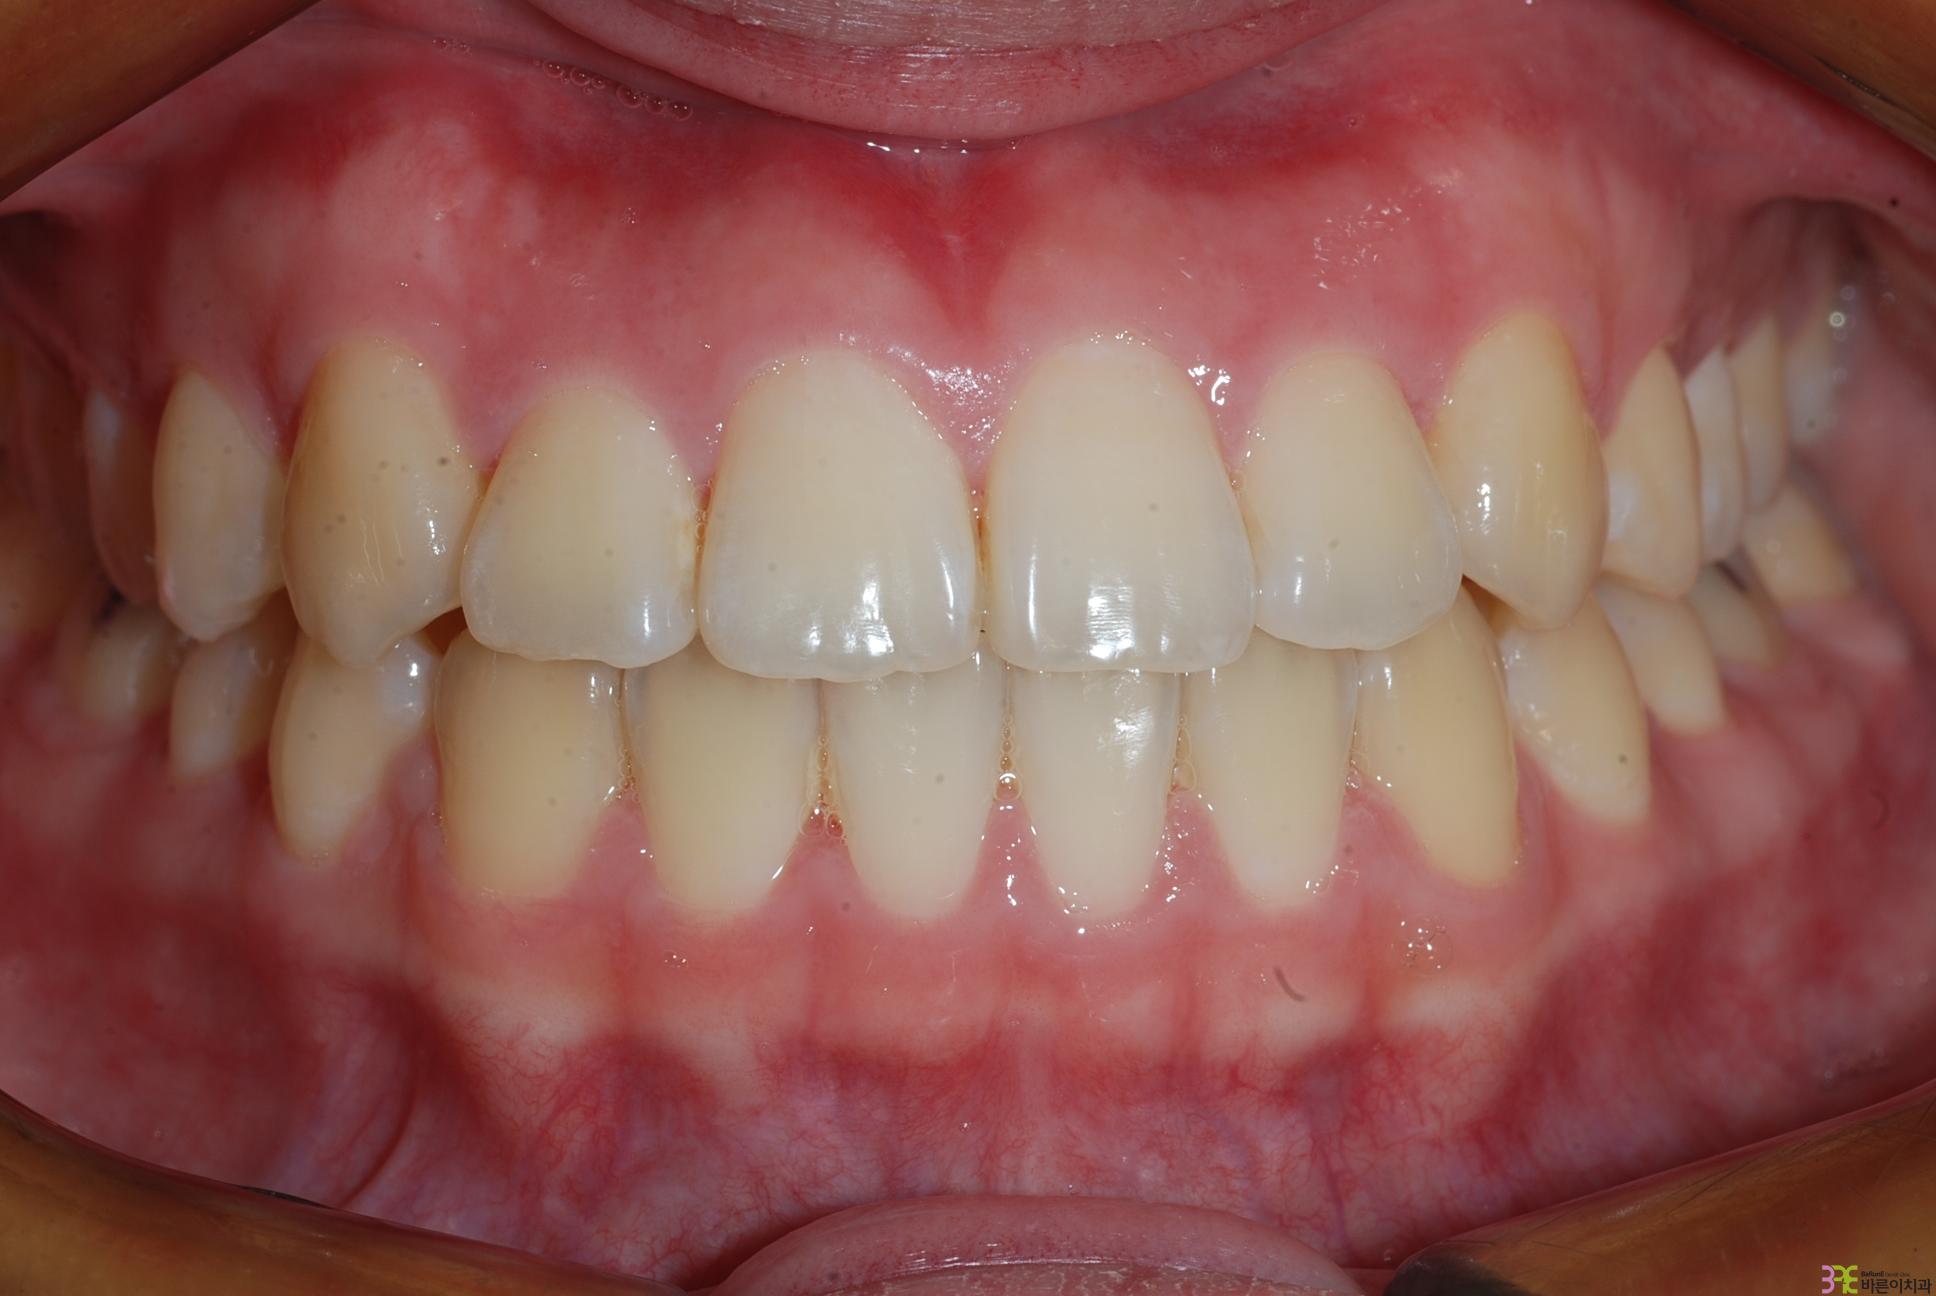

치료명

덧니 교정

치료기간

1년

Before

After